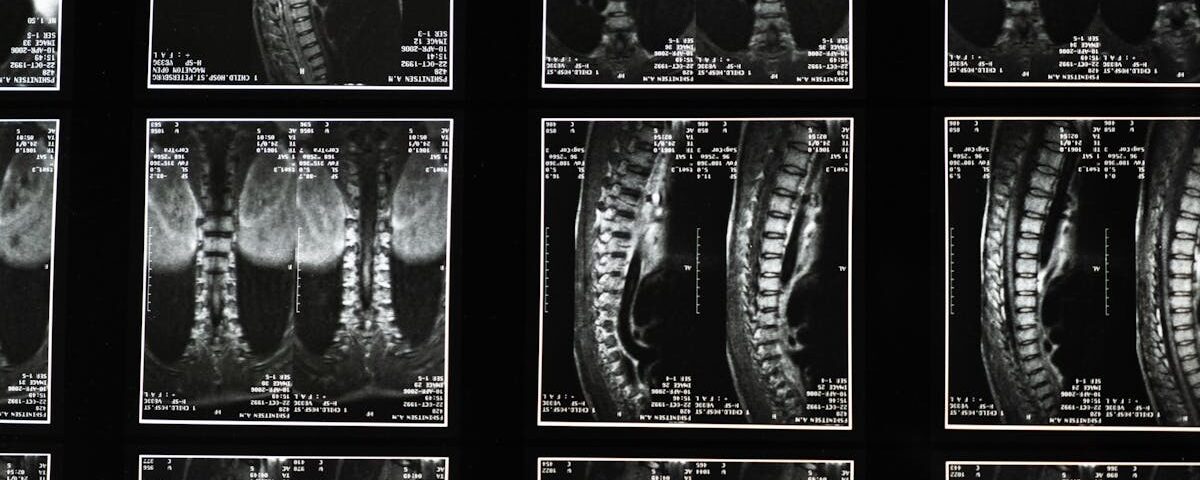

Quels examens permettent de diagnostiquer une protrusion discale?

Une IRM ou une radiographie est souvent nécessaire pour confirmer le diagnostic d’une protrusion discale.